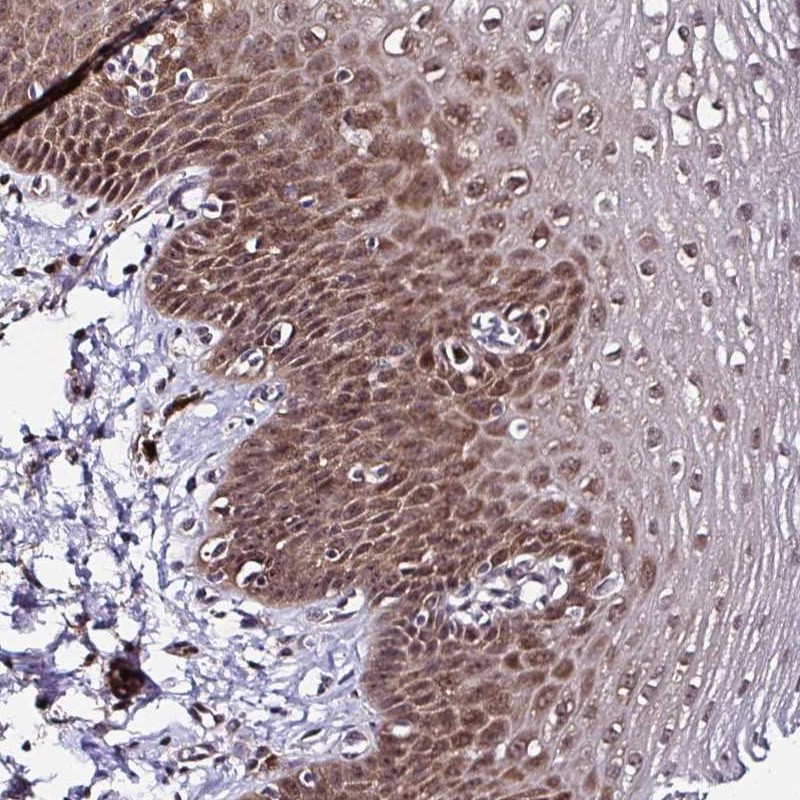

Immunohistochemical staining of human esophagus shows moderate cytoplasmic and nuclear positivity in squamous epithelial cells.